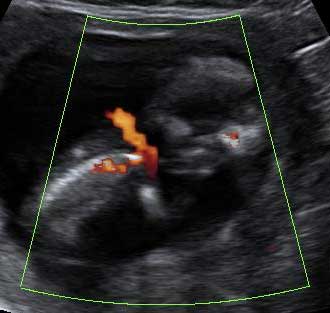

Detalle de los dedos de una mano de un feto de 12 semanas

Este bebé de 12 semanas de gestación, pone su mano en el campo de visión del ecógrafo. Por eso el especialista, comenta que "en condiciones favorables, como en este caso, pueden individualizarse los dedos". Efectivamente, podemos contar los cinco dedos del bebé, que se señalan con números en la imagen.